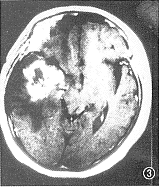

1.放射性脑坏死( radiation encephalic necrosis,REN):有4例5个病灶。右颞3个,左颞2个,1例为双侧。病灶在T1WI上呈大片不均匀低信号,T2WI上以高信号为主,中央有不规则等皮质信号区。注射Gd-DTPA后,病变区见明显强化灶,T2WI上的中央等信号区不强化,大小2.5 cm× 6.0 cm不等。其中4个完全或主要位于白质,1个累及灰质。病灶呈团块状,外形不规则呈粗大齿轮样。其中1 例手术病理提示该处为凝固性坏死。5 个病灶周围均见不同程度水肿,呈爪状沿白质蔓延;2个较重,波及同侧额顶及基底节区,占位效应显著;3 个较轻,只累及颞叶前中部,占位效应轻(图1~4)。

图1~4 为同一例患者。图1为T1WI,示右颞低信号灶,占位效应明显;图2为T2WI,示右颞额高信号灶,中部见等皮质T2信号区。图3,4示增强后病灶明显强化,内见非强化区,外观呈齿轮状,病灶主要累及白质